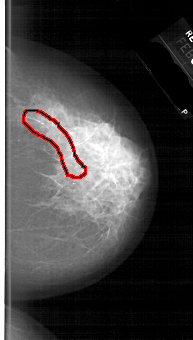

A_1667_1.RIGHT_MLO

FILE: A_1667_1.RIGHT_MLO.OVERLAY

TOTAL_ABNORMALITIES 1

ABNORMALITY 1

LESION_TYPE CALCIFICATION TYPE FINE_LINEAR_BRANCHING DISTRIBUTION SEGMENTAL

ASSESSMENT 4

SUBTLETY 4

PATHOLOGY MALIGNANT

TOTAL_OUTLINES 1

BOUNDARY